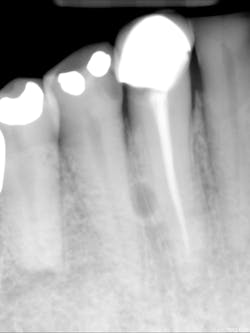

A complete mouth series was made with an incidental, well-defined, circular, radiolucent area noted between the roots of the mandibular right canine and first premolar.

For lateral periodontal cysts, there is a male predilection with a mean age of 50 years. They are typically asymptomatic and incidental findings. They are most commonly found between the lateral incisor and second premolar (mandible) and lateral incisor region (maxilla). The cyst appears as a well-defined, round/ovoid radiolucent entity. It may obliterate the lamina dura of adjacent teeth. As it enlarges, it may cause displacement and/or resorption of adjacent teeth. It is frequently single, but may be multiple. The size is typically less than 1 cm in diameter.

Differential interpretation includes keratocystic odontogenic tumor and lateral rarefying osteitis. Lateral rarefying osteitis will be associated with a nonvital tooth. The only way to determine the difference between a lateral periodontal cyst and a keratocystic odontogenic tumor is with histopathological diagnosis. Treatment is surgical excision.